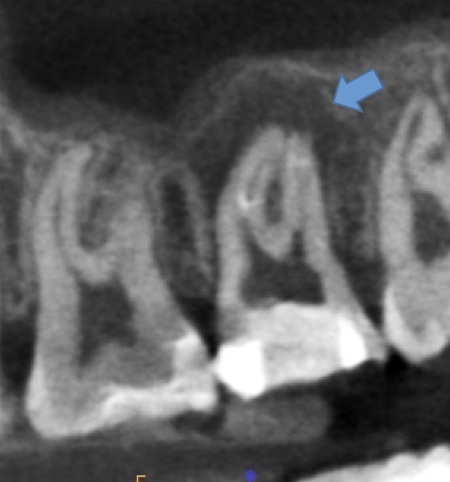

かぶせ物が不適であること(青矢印部)、近心根に根尖病巣があること(青枠部)、根充剤がかなり太いため(赤矢印部)歯質が薄くなっていることなど問題点がいくつかありましたが、他院で治療をしたばかりであり、また上記の条件から再治療には抜歯のリスクが非常に高いことから初診時は患者さんと相談し経過観察することになりました。